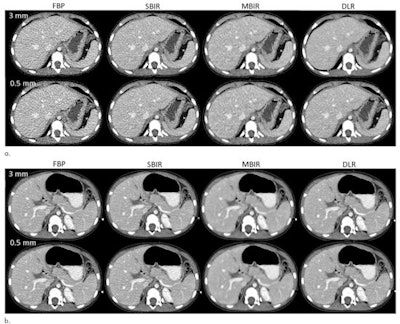

First, the researchers sent the raw data from these contrast-enhanced pediatric chest-abdomen-pelvis exams to Canon Medical Systems for offline image reconstruction. The raw data were reconstructed transaxially at 0.5- and 3-mm image thicknesses using Canon's FBP, Adaptive Iterative Dose Reduction 3D statistical-based iterative reconstruction (SBIR), FIRST Body Standard model-based iterative reconstruction (MBIR), and Advanced Intelligent Clear-IQ Engine (deep learning-based reconstruction) algorithms.

The researchers noted that deep learning-based reconstruction was able to reduce image noise without the noise texture effects experienced with MBIR. After performing two-way variance analysis, they also concluded that the difference in image quality ratings varied on the basis of reconstruction type (p < 0.001).